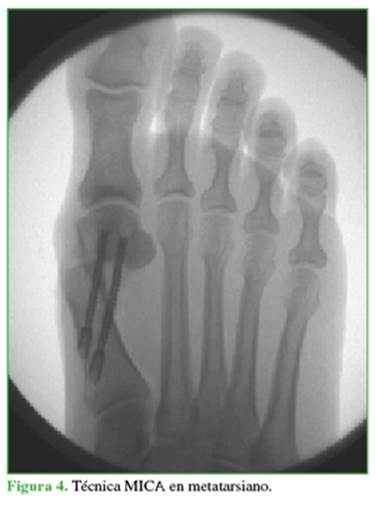

Resumen de la técnica de Bösch18 (modificada)

Paciente en decúbito dorsal. Liberación del tendón conjunto con técnica percutánea desde el primer espacio dorsal. Incisión paraungueal medial del primer dedo y avance de un alambre de Kirschner de 2,0 mm de diámetro hasta la metáfisis distal del primer metatarsiano. Portal metafisario distal medial del primer metatarsiano por donde se realiza una osteotomía transversal con fresa de corte tipo Shannon larga. Bajo control con intensificador de imágenes, se realiza la corrección angular metatarsiana (desplazamiento lateral) y se avanza el alambre de Kirschner endomedular hasta anclarlo en la base del mismo hueso. Estabilización percutánea con un tornillo canulado doble rosca de 3 mm, y síntesis de piel (Figura 3).